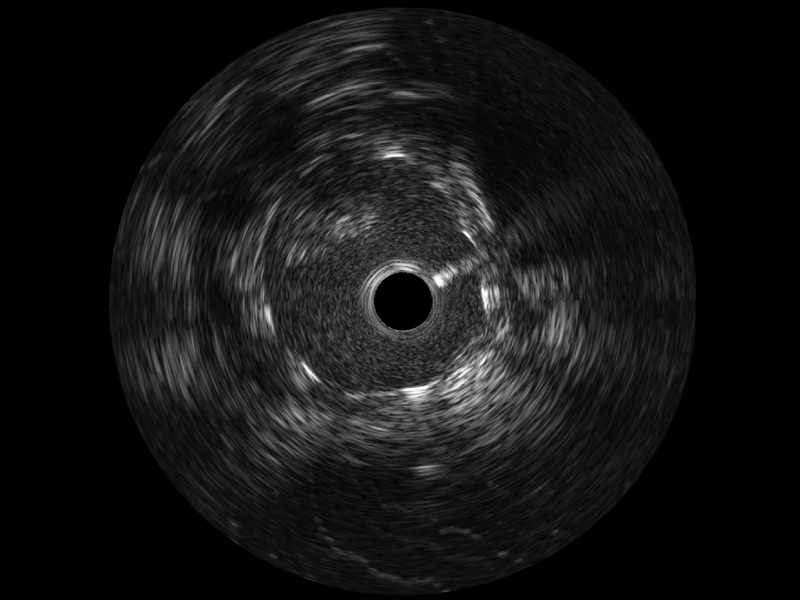

百老汇电子游戏官网宽频IVUS图像

传统IVUS图像

对比传统IVUS导管成像,百老汇电子游戏官网宽频IVUS图像的近场支架梁显影更细腻,远场中膜外血管仍清晰可辨,兼顾远中近,兼顾分辨力与穿透深度